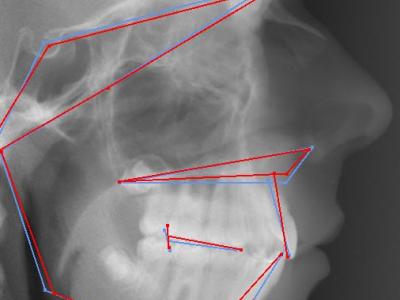

Téléradiographie de profil avant traitement (a),

téléradiographie de profil de réévaluation à 12 mois de traitement multi-attaches montrant l’aggravation de la proalvéolie mandibulaire avec IMPA=110° (b), l’affaiblissement labio-mentonnier est décidé à ce moment,

téléradiographie de profil en fin de traitement après 9 mois de finitions sur multi-attaches et 1 an de contention, l’IMPA est réduit à 100° et le muscle mentonnier s’est relâché (c),

superposition avec le logiciel Procuste (Rouge = Avant / Bleu = Après) montrant le redressement radiculaire des incisives mandibulaires et la croissance mandibulaire (d)

parodonte en fin de traitement (e).